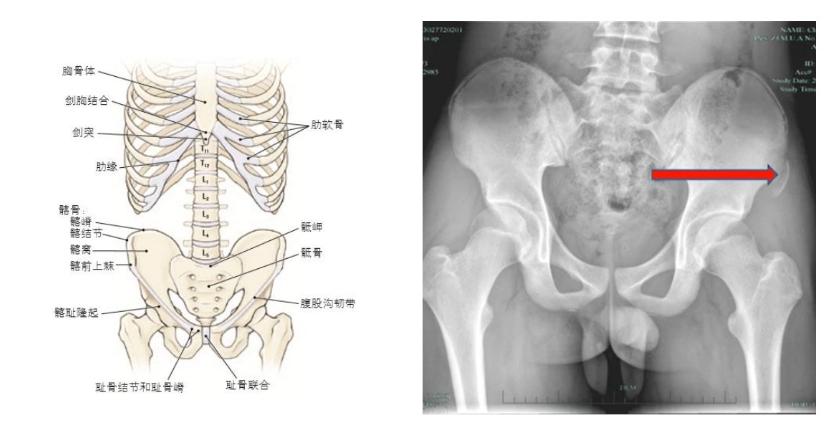

什么是髂前上棘?

髂前上棘,指的是髂嵴的前端。如果用专业术语解释会非常复杂,可以简单理解为大腿上方骨盆前侧的一块骨头。

通常来说我们不会用到它,更多是用来判断是否骨盆前倾。